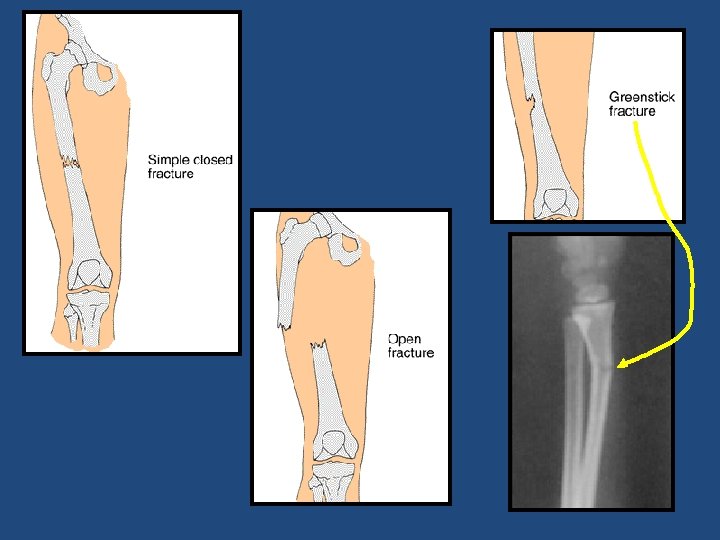

Fractures • Despite its mineral strength, bone may crack or even break if subjected to extreme loads, sudden impacts, or stresses from unusual directions. – The damage produced constitutes a fracture. • The proper healing of a fracture depends on whether or not, the blood supply and cellular components of the periosteum and endosteum survive.

Fracture Types • Fractures are often classified according to the position of the bone ends after the break: Open (compound) bone ends penetrate the skin. Closed (simple) bone ends don’t penetrate the skin. Comminuted bone fragments into 3 or more pieces. Common in the elderly (brittle bones). Greenstick bone breaks incompletely. One side bent, one side broken. Common in children whose bone contains more collagen and are less mineralized. Spiral ragged break caused by excessive twisting forces. Sports injury/Injury of abuse. Impacted one bone fragment is driven into the medullary space or spongy bone of another.